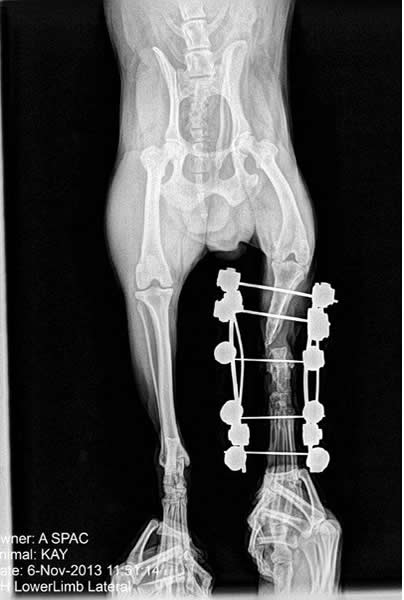

KAY

Kay fue recogido en Ribera de Cabanes. Tenía una antigua cirugía en su pata trasera

izquierda. La prótesis se rompió y Kay vivía en la calle con un agujero en su pata por donde se

salía la prótesis. El dueño era consciente de su estado y permitía que viviera en estas

condiciones. Tras ser rescatado por ASPAC, Kay fue tratado contra la Leishmania y fue intervenido quirúrgicamente

para frenar la infección de su pata.

Tras retirársele los hierros de la operación, Kay será operado de nuevo

para reconstruir su pata.